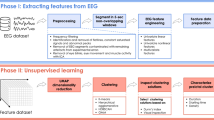

Fundamental problems in data mining mainly involve discrete decisions based on numerical analyses of data (e.g., class assignment, feature selection, data categorization, identifying outlier samples). These decision-making problems in data mining are combinatorial in nature and can naturally be formulated as discrete optimization problems. One of the most widely studied problems in data mining is clustering. In this paper, we propose a new optimization model for hierarchical clustering based on quadratic programming and later show that this model is compact and scalable. Application of this clustering technique in epilepsy, the second most common brain disorder, is a case point in this study. In our empirical study, we will apply the proposed clustering technique to treatment problems in epilepsy through the brain dynamics analysis of electroencephalogram (EEG) recordings. This study is a proof of concept of our hypothesis that epileptic brains tend to be more synchronized (clustered) during the period before a seizure than a normal period. The results of this study suggest that data mining research might be able to revolutionize current diagnosis and treatment of epilepsy as well as give a greater understanding of brain functions (and other complex systems) from a system perspective.